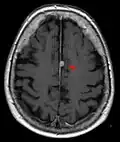

Kontrastmittel aufnehmendes Meningeom der linken Hemisphäre in der Computertomographie -

Typische randständige Lokalisation eines Meningeoms rechts (Kernspintomographie, T1-gewichtet mit Kontrastmittel) -

Das bildgebende Verfahren der ersten Wahl ist beim Meningeom heute die Kernspintomografie, da dieses Verfahren den größten Weichteilkontrast besitzt und in typischen Fällen die sichere Diagnose eines Meningeoms ermöglicht. In T2-gewichteten Aufnahmen stellen sich verkalkte Meningeome im Gegensatz zu vielen anderen Tumoren als schwarze Masse (hypointens) dar, die dunkler als das umgebende Hirngewebe ist. Unverkalkte Meningeome können zur Umgebung isointens sein. Von anderen Tumoren unterscheiden sich Meningeome durch ihre Lage auf der Dura mater mit charakteristischen Ausläufern in die Dura (dural tails) und durch eine sehr intensive Kontrastmittelaufnahme. Die Computertomographie kann die Tumorverkalkungen sehr gut nachweisen. Konventionelles Röntgen und Angiographie haben heute nur noch eine untergeordnete Bedeutung.